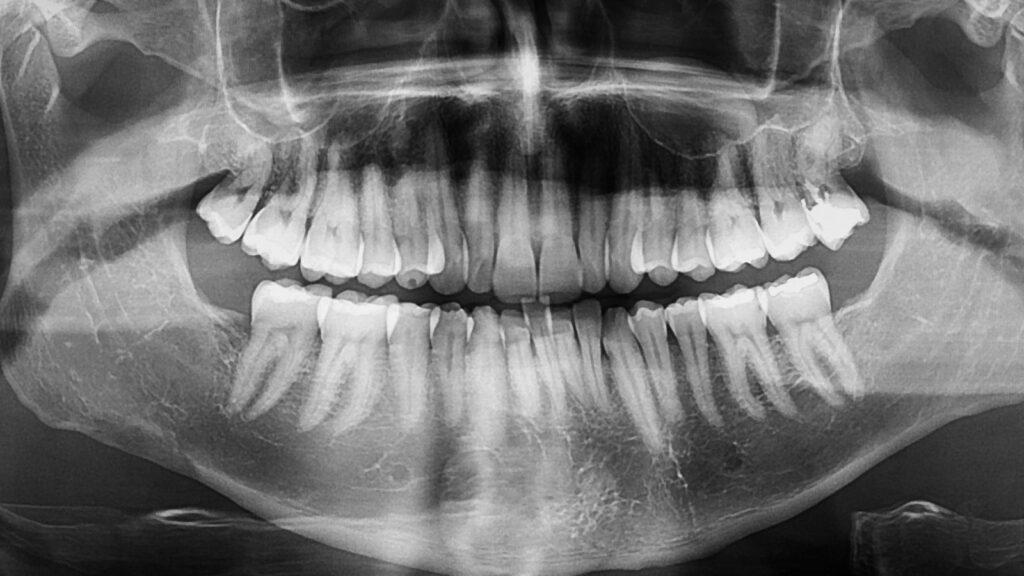

目で見えない歯の根の状態や、歯と歯の間の虫歯、顎の骨の状態などを正確に把握するためには、レントゲンによる画像診断が必要です。

レントゲンなしで治療を進めると、見落としがあったり、不適切な治療方法を選択してしまったりするリスクがあります。

例えば、歯の根の先に膿が溜まっている場合、レントゲンで確認しなければ正確な診断ができず、治療が長引いてしまいます。